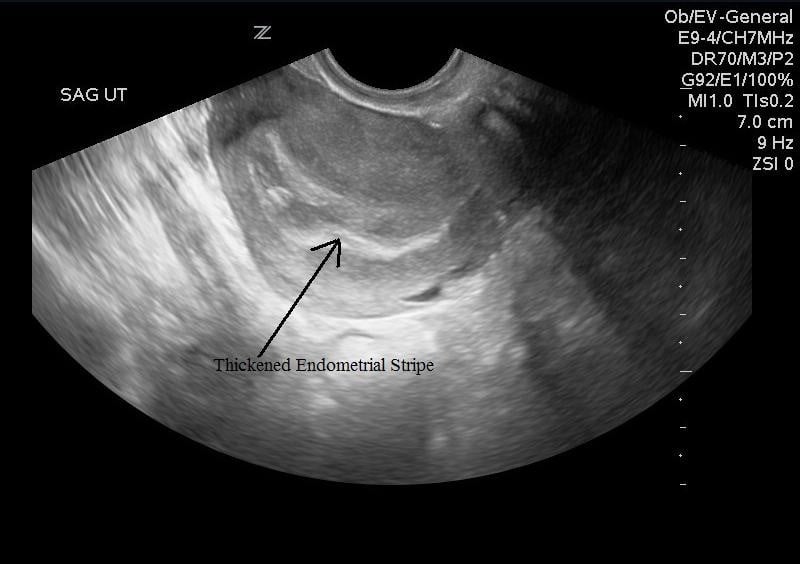

In most cases, an ultrasound scan can determine if you're having a miscarriage. The signs of early miscarriage will depend on the gestation of your pregnancy. It may feel crampy or persistent,.